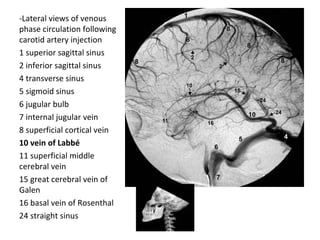

-Lateral views of venous

phase circulation following

carotid artery injection

1 superior sagittal sinus

2 inferior sagittal sinus

4 transverse sinus

5 sigmoid sinus

6 jugular bulb

7 internal jugular vein

8 superficial cortical vein

10 vein of Labbé

11 superficial middle

cerebral vein

15 great cerebral vein of

Galen

16 basal vein of Rosenthal

24 straight sinus